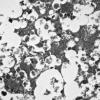

8I2 Granular Cell GBM (Case 8) EM 020 - Copy